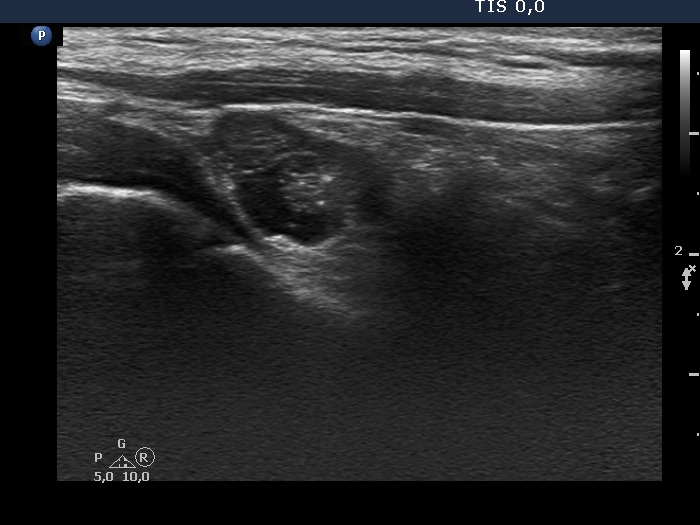

Ultrasound. Connective tissue replaced the thyroid parenchyma in both thyroid beds. There was a hypoechoic mass in the lower part of the right thyroid bed dorsal to the carotid artery. The lesion was a mixed, dominantly solid nodule and had microcalcifications.

Aspiration cytology from the hyperechogenic lesion resulted in papillary cancer. Wash-out thyroglobulin was 6905 ng/mL